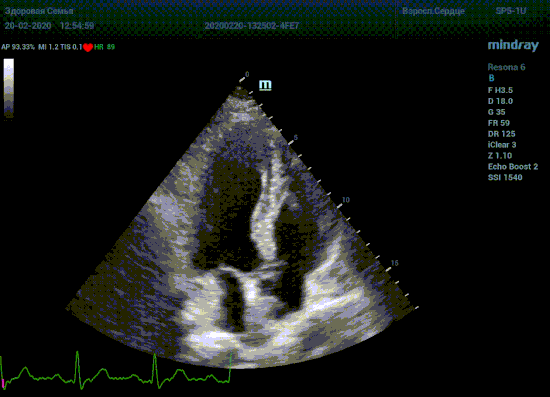

Специалисты в области эхокардиографии прекрасно знают о важности точного и скрупулёзного измерения. Рекомендации зарубежных кардиологических и эхо кардиографических обществ описывают эхокардиографию только под контролем ЭКГ. Многие клиники в России до сих работают без ЭКГ канала, выбирая кадры для измерения «на глазок». Результаты таких исследований менее точны и воспроизводимы, однако роль их очень и очень велика. Часть клиник используют ЭКГ отдельно от прибора, на бумаге. В таком виде для эхокардиографии она бесполезна, по сколку не создает временной карты для измерений.

Подбор подобающей терапии и оценка её динамики на базе расчета массы миокарды рутинная задача эхокардиографии. Для измерения массы нужен кадр конца диастолы. На глазок или точно, по ЭКГ каналу, выбрать диастолу? Гипертрофия миокарда или его ремоделирование? Ремоделирование или норма? Решает каждый измеренный миллиметр, даже каждая его десятая. Лишние доли секунды приведут к началу сокращения миокарда и его утолщению, в результате -гипердиагностика.

Терапия наиболее широкая область применения, однако взрослая кардиохирургия так же важное направление современной медицины. Оперировать аортальный стеноз, или же площадь клапана достаточная? Необходимо рассчитать площадь аортального клапана по уравнению непрерывности потока. Для этого нужно измерить на зуме выносящий тракт левого желудочка (LVOT) в середине систолы. Будем угадывать момент или возьмем середину Т зубца по ЭКГ? Доверимся интуиции при определении показаний к оперативному лечению или науке?

Детская кардиохирургия не исключение. Наиболее актуальная проблема — это дефекты межпредсердной и межжелудочковой перегородок, а также открытый артериальный проток. Не верная оценка гемодинамической значимости приведет к перегрузке правых отделов сердца и ряду осложнений, в случае если не прооперировать вовремя. Отправлять маленького ребенка под нож или подождать пока дефект перегородки зарастет сам? Ждем осложнений или ждать безопасно? На эти вопросы ответит Qp/Qs соотношение, рассчитанное методом эхокардиографии. Для этого необходимо рассчитать ударные объемы выносящих трактов желудочков, опять же на середине систолы – середине Т–зубца ЭКГ.